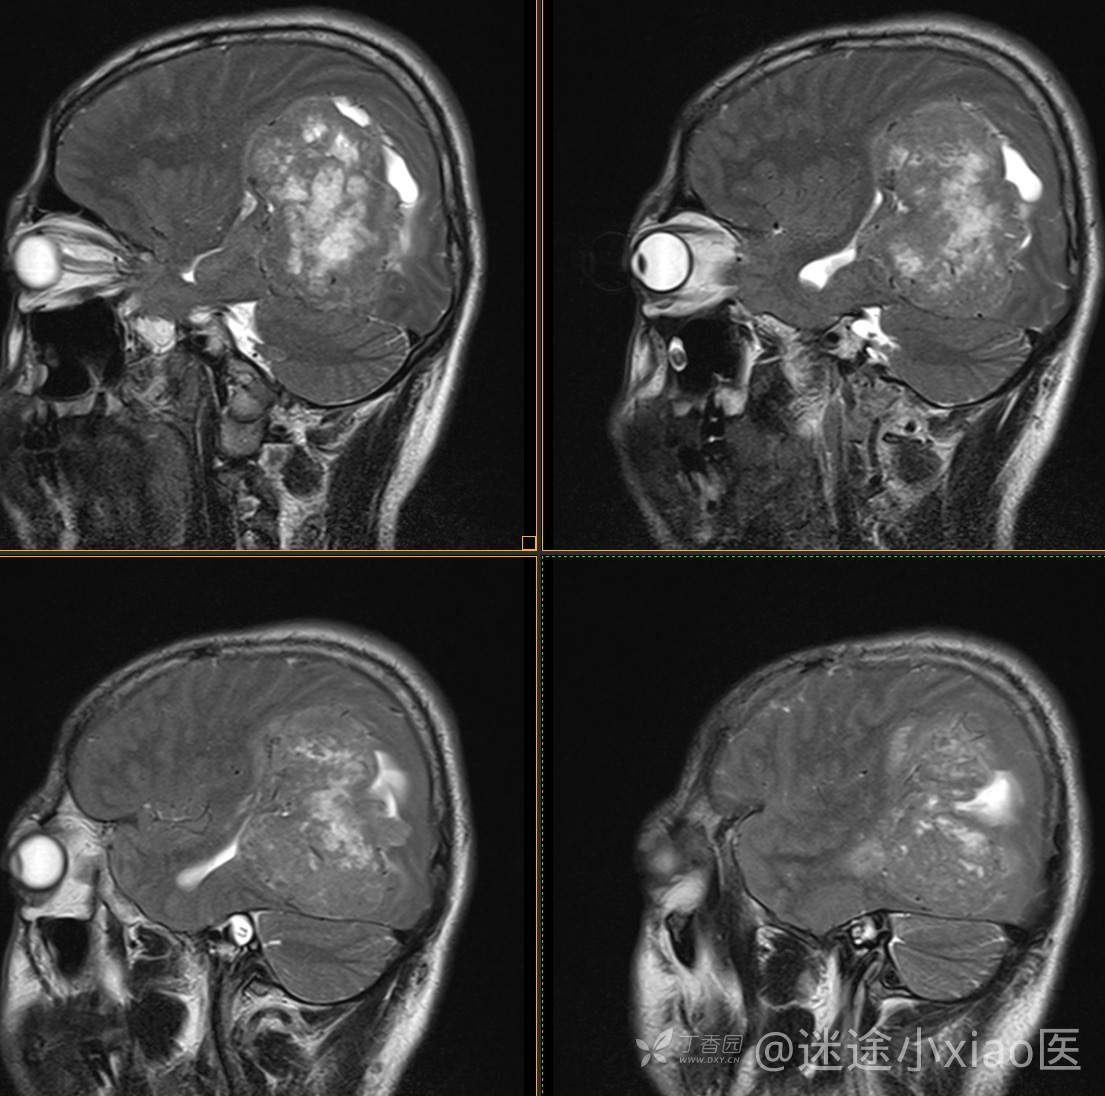

患者年龄:43

患者性别:男

简要病史:头痛3月余,查体无殊